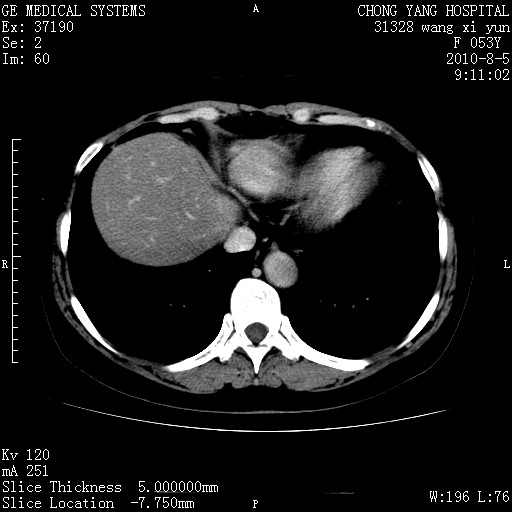

标题: CT28214:F41Y 血尿二十天,建议盆腔平扫加增强。

1)考虑肝左叶胆管细胞癌。2)脂肪肝。